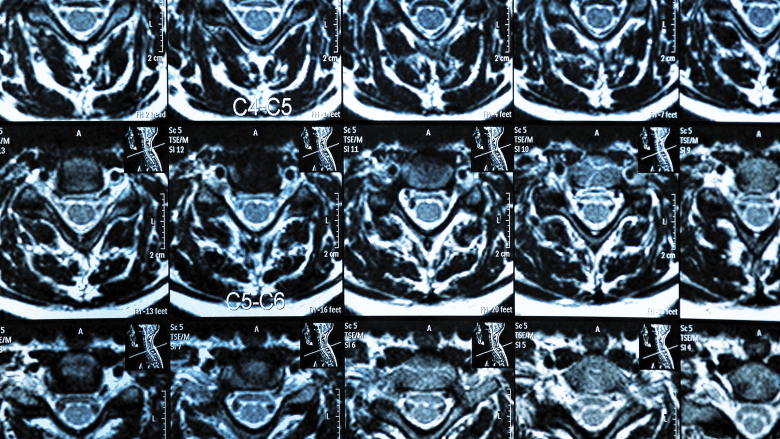

MRI scan of the cervical spine showing multiple spinal segments